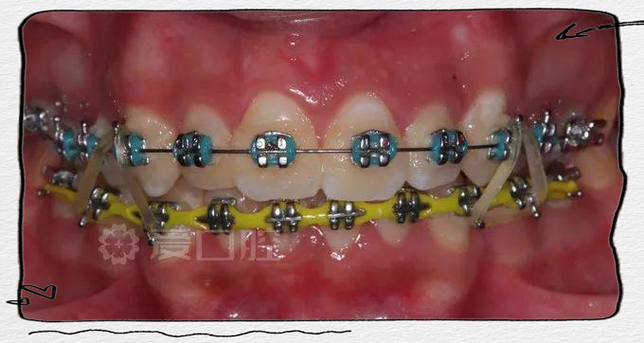

- 关闭间隙阶段的牵引力不平衡:在关闭拔牙间隙时,医生常使用滑动法或关闭曲法施加牵引力,若牵引钩位置不对称、牵引力大小不一致(如橡皮圈牵引时两侧力量不均),会导致间隙关闭速度不同,弓丝随之向间隙关闭较慢的一侧偏移。

- 辅助装置使用:对于因牙弓不对称或咬合异常导致的弓丝偏移,医生可能会添加辅助装置,如螺旋弹簧(调整间隙)、橡皮链(关闭间隙)、颌垫(纠正咬合)等,平衡两侧受力。